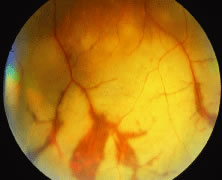

Progression of the retinitis generally occurs with a leading edge of active retinitis and a trailing region of thin gliotic retina. This pattern indicates cell to cell transmission of the virus. CMV is a slowly progressive, necrotizing retinitis that may affect the posterior pole, the peripheral retina, or both and may be unilateral or bilateral. Involved areas appear as white intraretinal lesions; areas of infiltrate; and often necrosis, along the vascular arcades in the posterior pole. In addition, prominent retinal hemorrhages are often seen within the necrotic area or along its leading edge (Figs. 12 and 13). Peripherally, CMV retinitis tends to have a less intense white appearance, with areas of granular, white retinitis that may or may not demonstrate associated retinal hemorrhage (Fig. 14). As the retinitis progresses, an area of atrophic, avascular retina may remain with underlying retinal pigment epithelial atrophy and/or hyperplasia (Fig. 15).57,58,60,62 Peripheral CMV retinitis may be the most common form of CMV retinitis seen. Patients may initially complain only of floaters with or without a visual field deficit.57 Wide-angle fundus photography and fluorescein angiography may be of benefit when the diagnosis is uncertain. These techniques may be used to document progression of retinitis, and fluorescein leakage in areas of retinitis may be helpful in confirming the diagnosis. Although peripheral CMV retinitis may not pose an immediate threat to vision, initiation of treatment should be seriously considered because several investigators have shown that untreated CMV retinitis is inexorably progressive and becomes bilateral in virtually all untreated patients.59,60,65,74–76 Occasionally, noncontiguous areas of new retinitis may be seen. As healing takes place, a thin glial scar replaces the necrotic retinal tissue. The transition from infected to noninfected retina is usually sharply demarcated and well seen during the active phase of the disease. When healing takes place, the transition zone is between a glial scar and normal retina and may be difficult to visualize. Clinically, the pigment epithelium tends to develop a characteristic spiculated granular appearance directly under the residual glial scar. The retina in the immediately adjacent uninvolved areas is thick in comparison to the glial scar, thus, differing light reflexes occur with indirect ophthalmoscopy. Using the pigment epithelium pigment changes and light reflexes, one can define the extent of prior retinal involvement. More importantly, defining the edge of prior involvement allows one to predict with great accuracy the sites of new involvement, allowing for more effective monitoring of therapeutic efforts to control the infection. Other manifestations of CMV retinitis include retinal edema, attenuated vessels, perivascular sheathing, and exudative retinal detachment.77 In addition, vitreitis and anterior uveitis are often seen,70 and optic atrophy may occur as a late manifestation secondary to widespread retinal destruction. CMV may be demonstrated in vitreous biopsy specimens in these patients.65 The yield may be higher in the presence of marked vitreitis because CMV is a cell-associated virus. Other causes of retinitis, including herpes simplex retinitis,78,79 toxoplasmosis,80 Candida, Behçet's disease, syphilis, ARN,7,28,81 and SSPE82 can usually be distinguished from CMV on clinical grounds. Cotton-wool spots are nonspecific and may be seen in diabetes mellitus, hypertension, severe anemia, systemic lupus erythematosus, dermatomyositis, and leukemia,83,84 as well as AIDS. It may be difficult to distinguish a small focus of nonhemorrhagic CMV retinitis from a cotton-wool spot corresponding to the area of peripapillary optic nerve fiber layer that was destroyed (Figs. 16 and 17). In eyes in which CMV infection initially involves the optic nerve head, the visual acuity may be normal early; however, the visual prognosis may be poor because these eyes often go on to loss of light perception (see Fig. 13). When retinitis is in close proximity to the optic nerve head or macula, a serous retinal detachment may be seen that will resolve with therapy.

Fig. 12. A patient with a relatively nonhemorrhagic variant of cytomegalovirus retinitis. Note at the center of the lesion (oldest area of infection) the retina is atrophic and pigmentary changes can be seen. Peripheral to it the retina is edematous, and this is the area of active infection.

Fig. 13. A patient with hemorrhagic variant of cytomegalovirus (CMV) retinitis that affected the posterior pole and optic nerve. Hemorrhages are most often intraretinal, and white areas correspond histologically to intracellular and extracellular edema and necrosis of the neurosensory retina. Eyes with extensive optic nerve involvement secondary to retinal involvement may still retain good central vision unless the papillomacular bundle is involved. When retinitis starts in the optic nerve head, the prognosis for vision is poor.